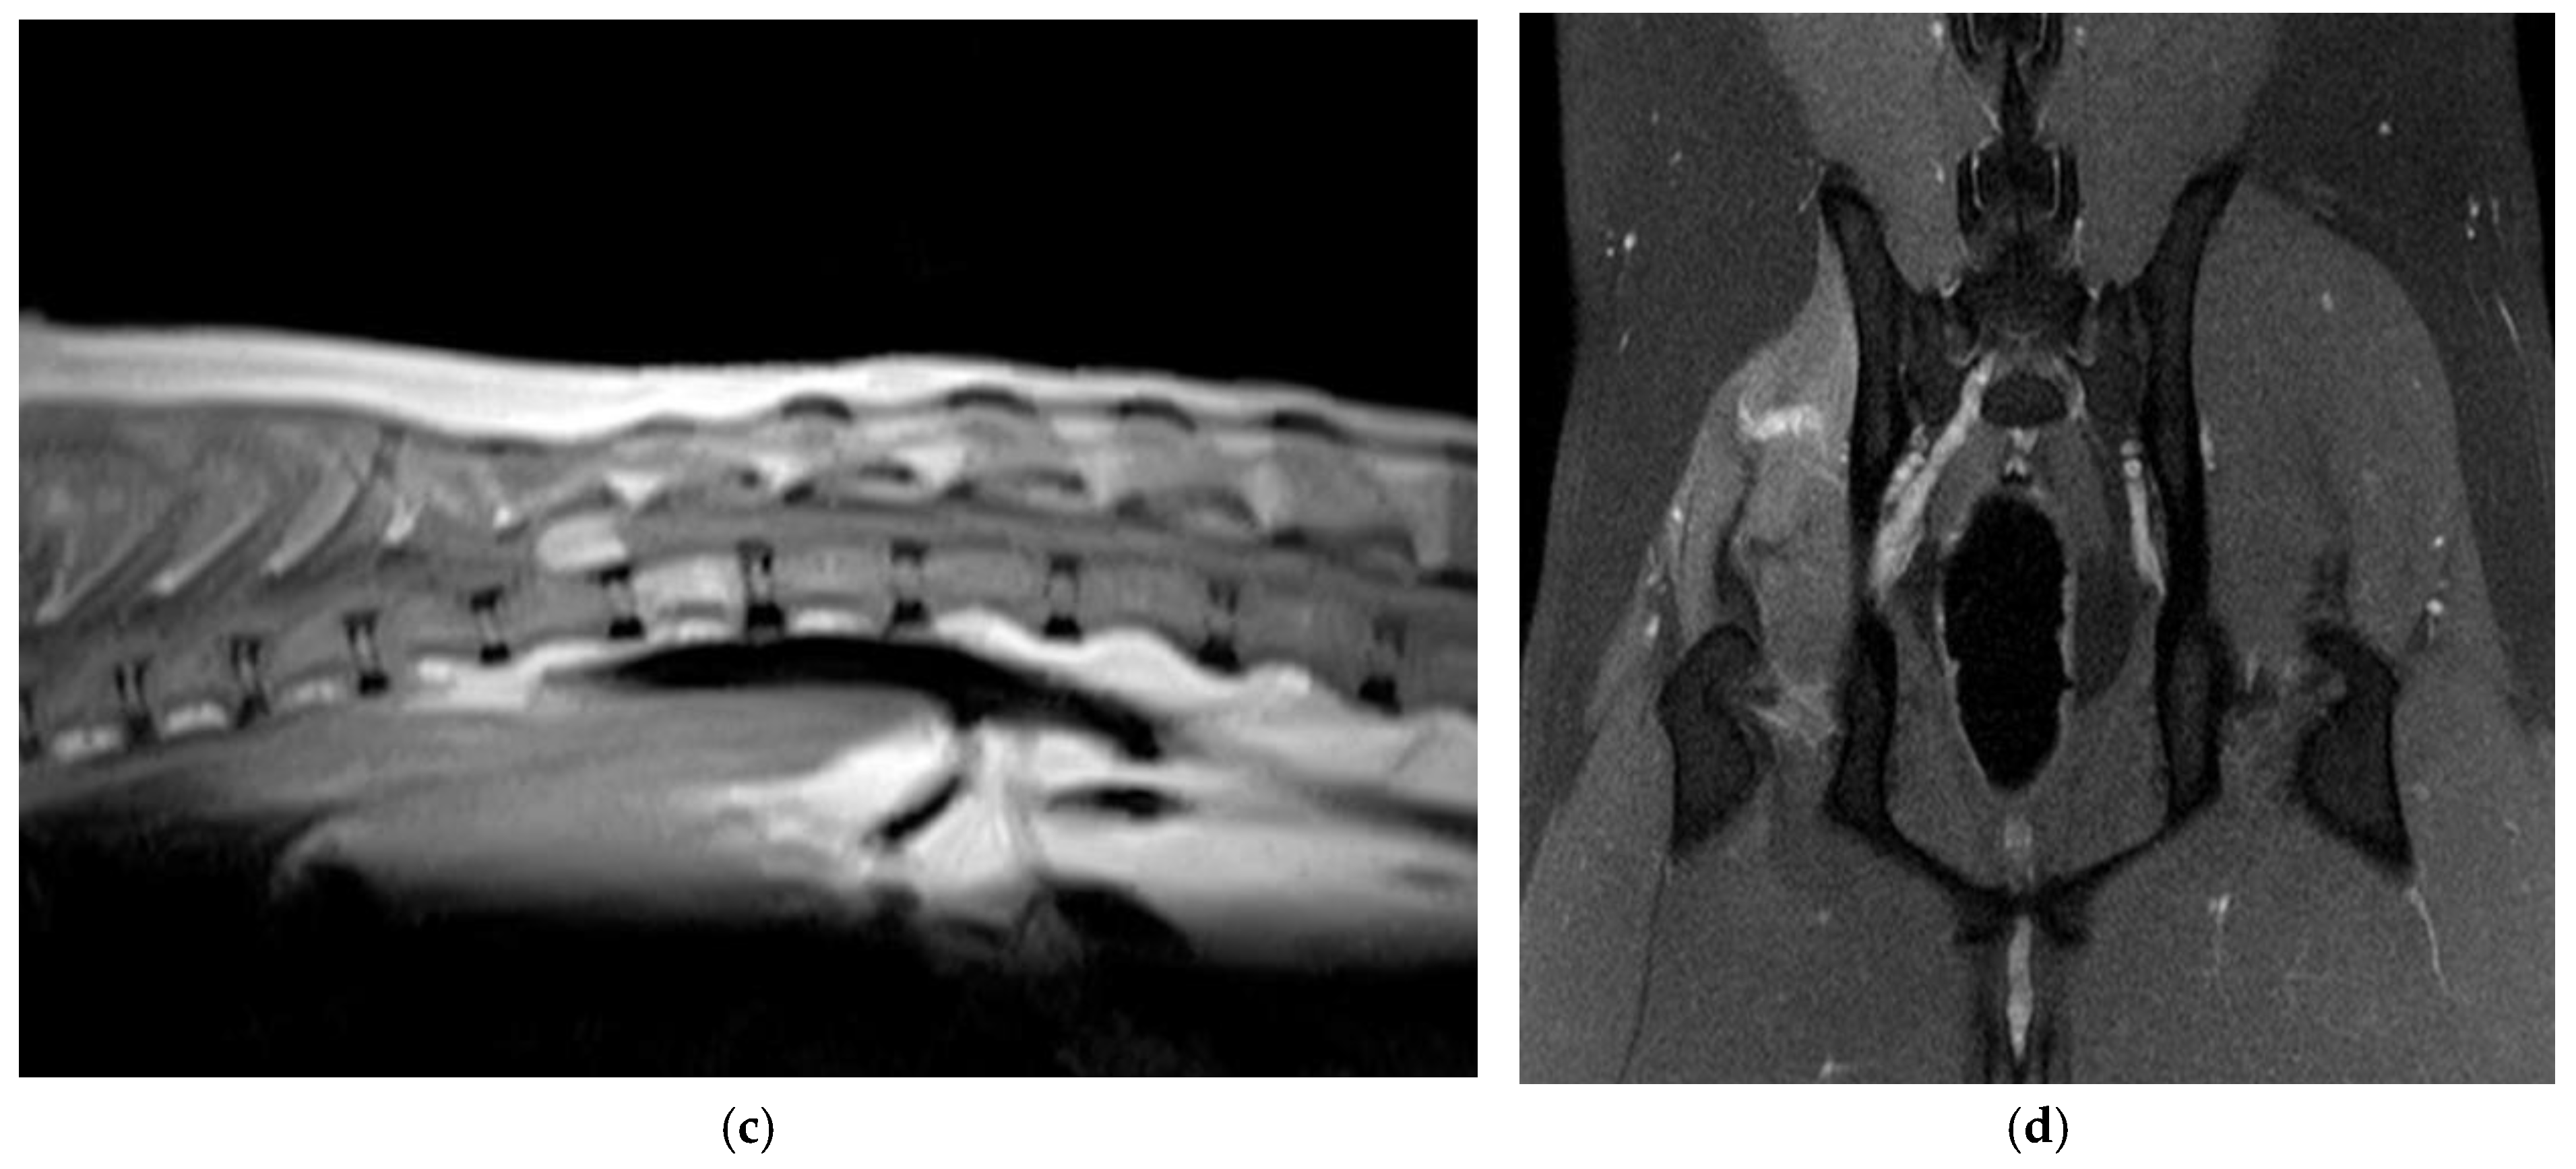

3.1. Clinical and Imaging Findings

3.2. Pathological Findings